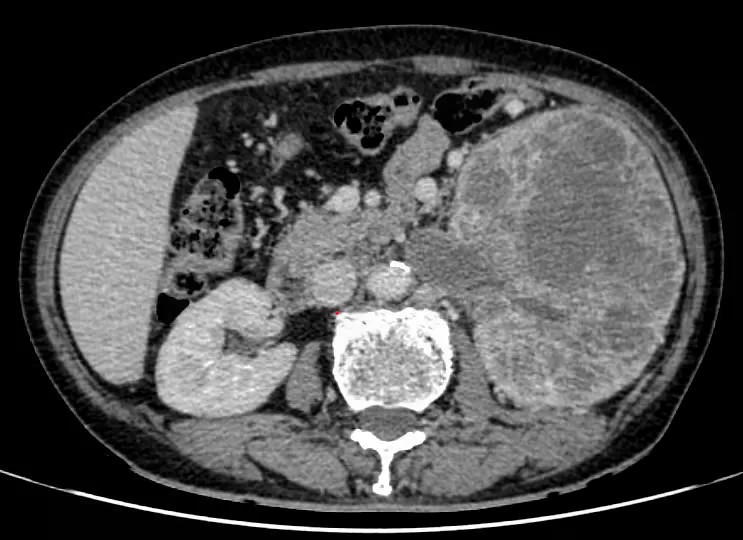

Kết quả thăm khám và chẩn đoán hình ảnh cho thấy khối u ở thận trái kích thước khoảng 15x20 cm, phá hủy hoàn toàn cấu trúc nhu mô thận, xâm lấn đài – bể thận.

Đáng chú ý, khối u đã gây huyết khối trong tĩnh mạch thận, lan tới tĩnh mạch chủ dưới, làm tăng nguy cơ tắc mạch hoặc thuyên tắc mạch phổi đe dọa tính mạng.

Hình ảnh chụp CT khối u ở thận xâm lấn tĩnh mạch chủ dưới - Ảnh BVCC